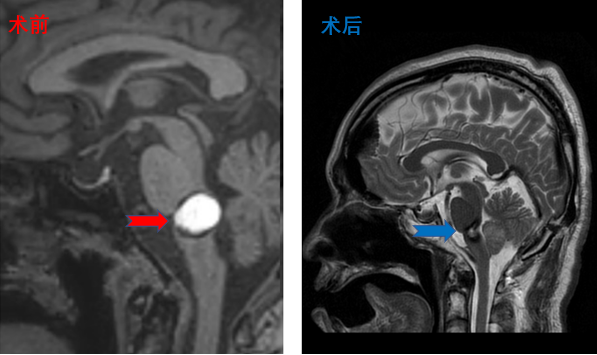

颅咽管瘤患者影像,患者术后视力明显改善,无明显尿崩及电解质紊乱

脑干海绵状血管瘤患者影像,术后肢体活动良好、面瘫情况同术前,无新增阳性体征